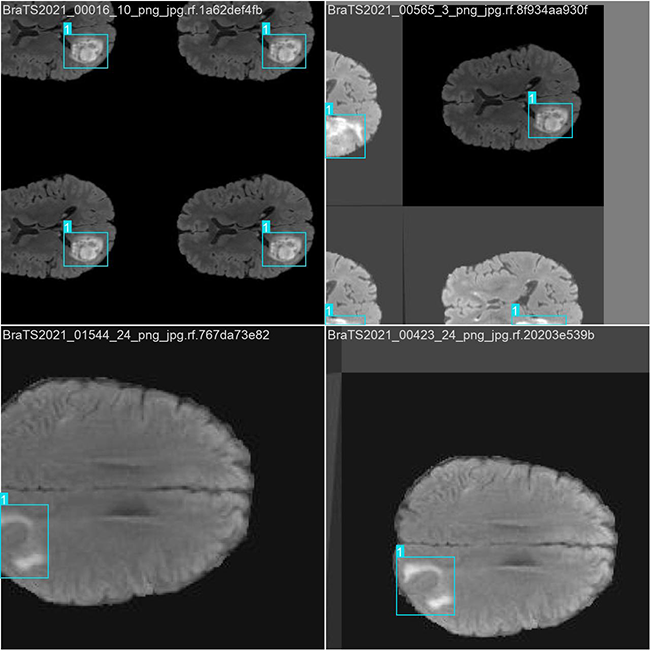

部分数据集图像如下图所示:

部分标注如下图所示: